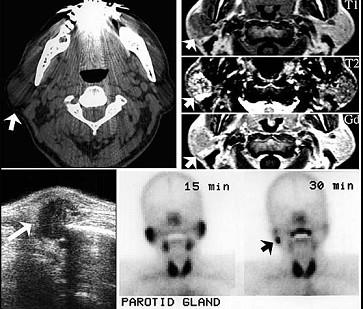

60岁男性,左耳垂下无痛性肿物缓慢长大四年,局部有胀感。检查见肿块位于腮腺后下极,表面光滑,质中偏软,不可压缩,与皮肤无黏连。影像检查结果如图。最可能的诊断是 ( )

A腮腺血管瘤

B腮腺多形性腺瘤

C腮腺沃辛瘤

D腮腺内淋巴结炎

E腮腺囊肿